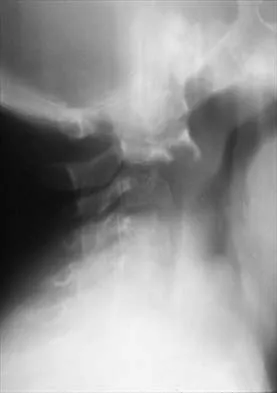

Figure 16 shows the radiograph of a 56-year-old man who has neck pain after a rollover accident on his lawnmower. The injury appears to be isolated, and he is neurologically intact. Management of the fracture should consist of

Explanation